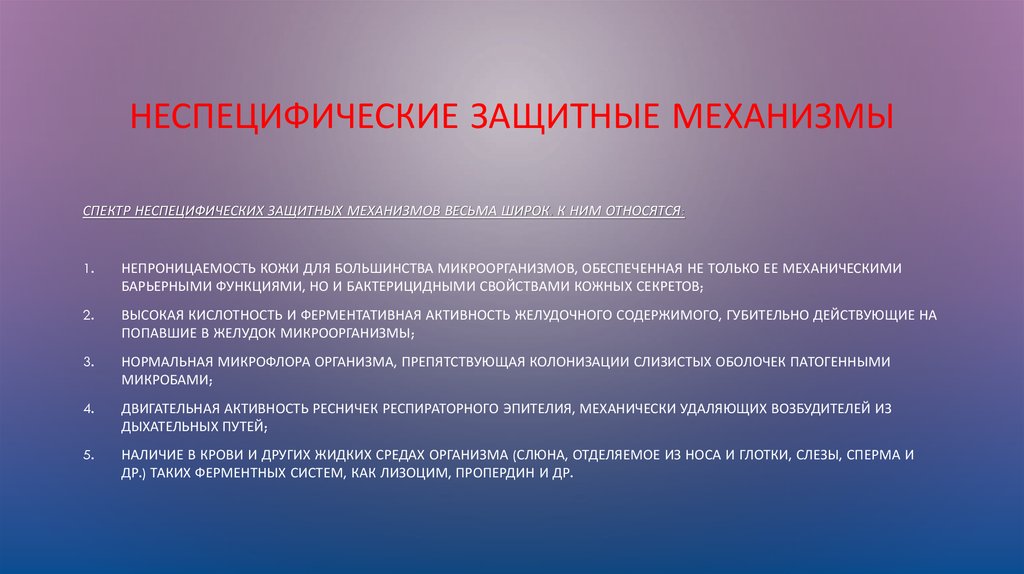

Фотографии символов защиты: разгадка механизмов замещения

Раздел: Снимки-откровения